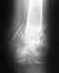

Перелом пятки. Если есть возможность сделать малоинвазивный остоетсоинтез - то сделать, если нет - можно и консервативное, результат должен быть удовлетворительный.